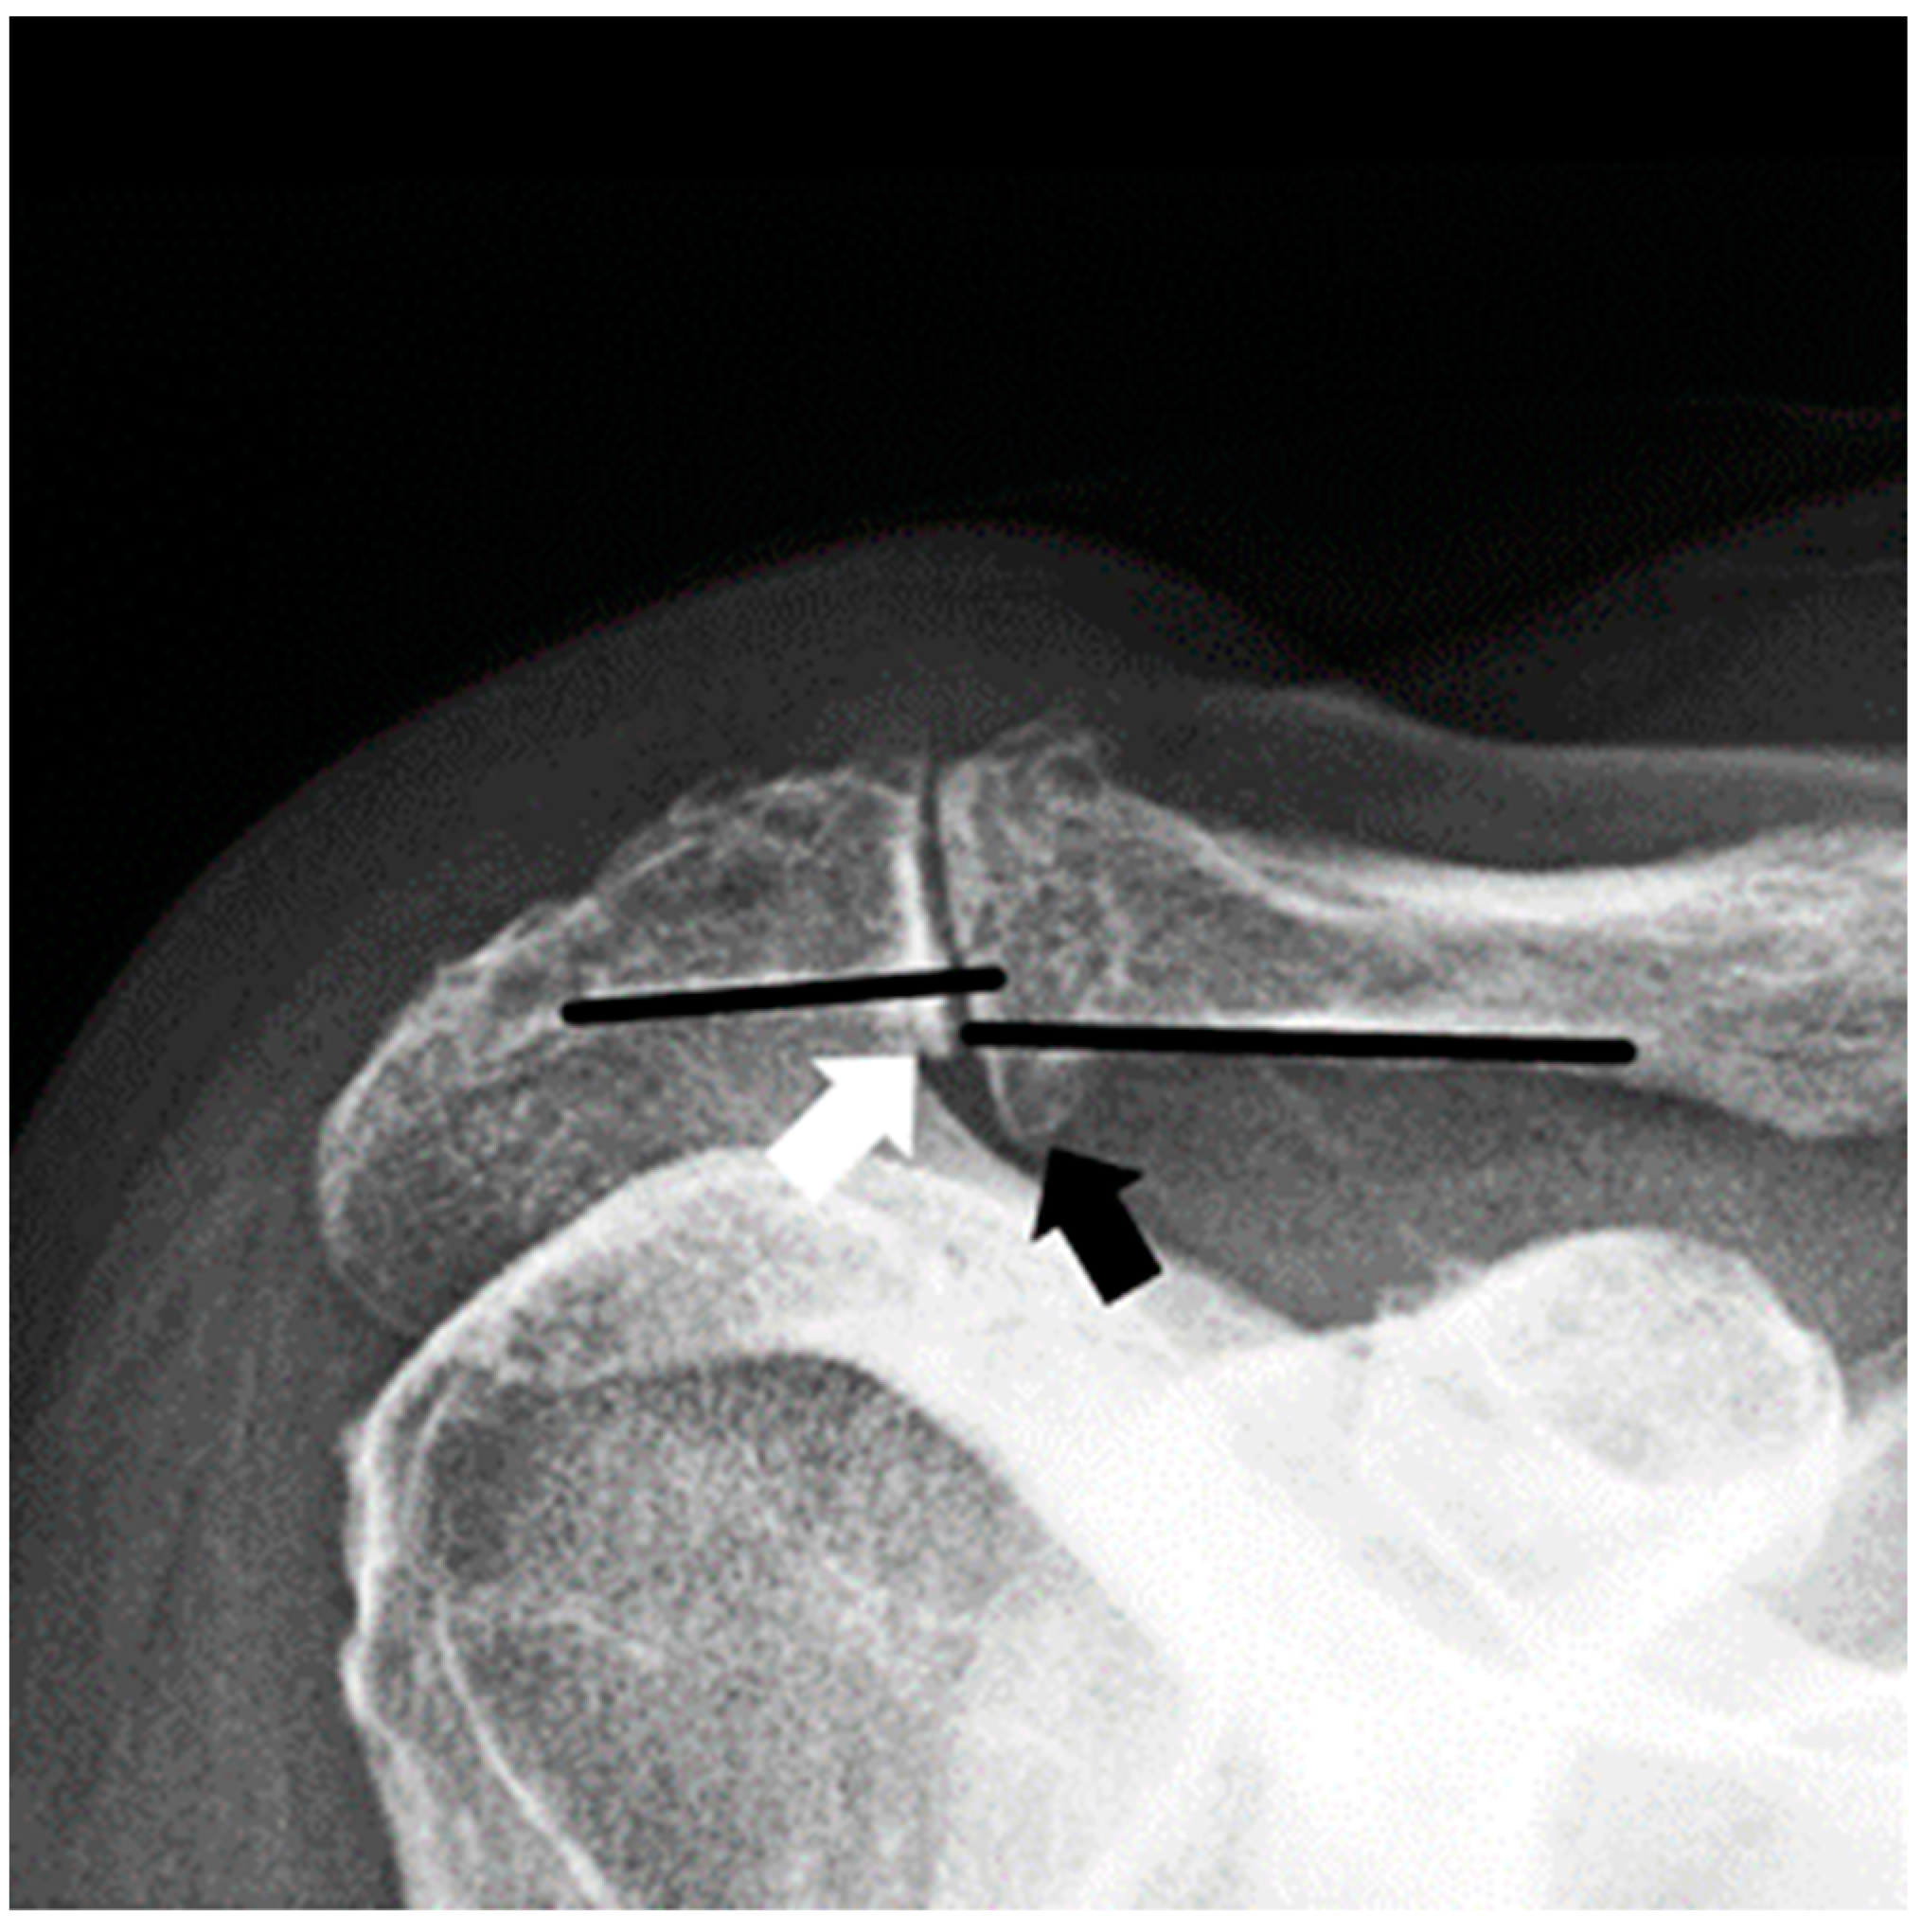

3.1. Radiographic Assessment